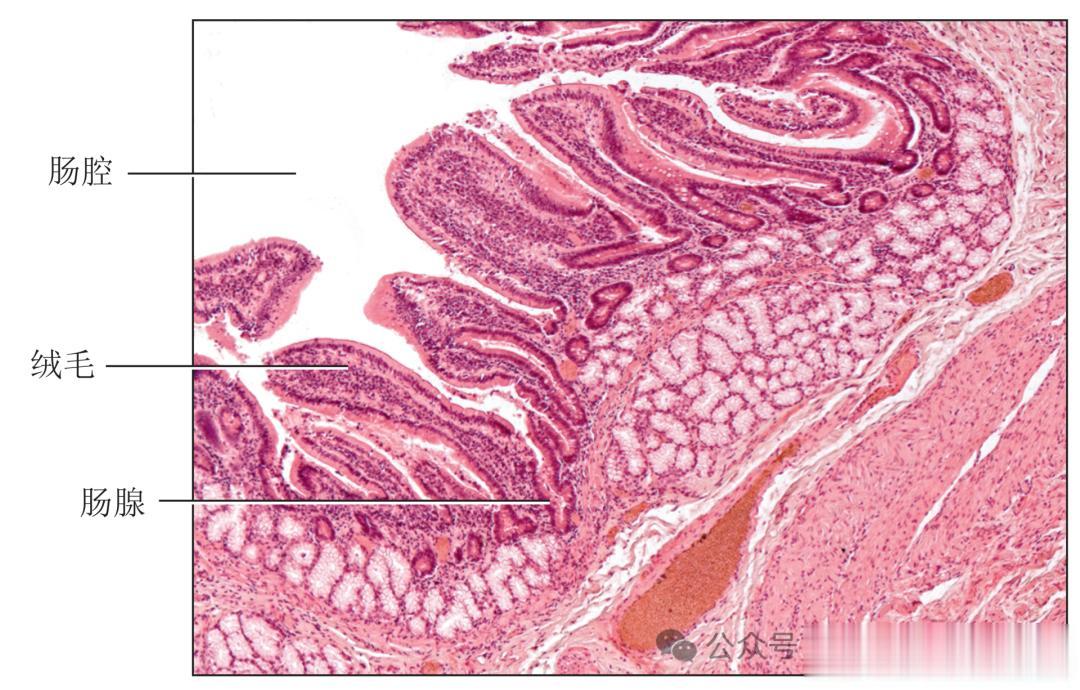

十二指肠壁肠绒毛的光学显微照片(50倍)